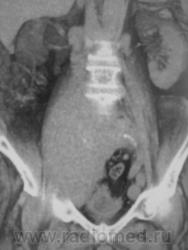

Мужчина 82 года, поступил в гнойное отделение с диагнозом: тромбофлебит? Правая нижняя конечность вдвое увеличена в объеме. Хирург отделения заподозрил опухоль таза с компрессией сосудов. По УЗИ - забрюшинная опухоль.         КТбрюшной полости: от L3 справа мягкотканная однородная опухоль с четкими ровными контурами, спускается в таз и на бедро. Плотность 45 ед.Н. Оттесняет мочевой пузырь, петли подвздошной кишки, не дифференцируется от нижней полой вены и подвздошных сосудов (нативно). Генерализованное поражение лимфоузлов брющной полости, паховые до 3-4 см. Гидронефроз справа, мочеточник оттеснен образованием значительно кпереди, на уровне L5 камень мочеточника 0.7см. Без контрастирования. Планировала на 5 апреля болюсное контрастирование, но пациента 2 апреля выписали!

Может, кто видел подобное? Велика вероятность злокачественной забрюшинной опухоли, но в 82 года такая генерализация лимфоузлов! Цитология паховых лимфоузлов в работе.

фронтальные реконструкции, плоскостные и объемные